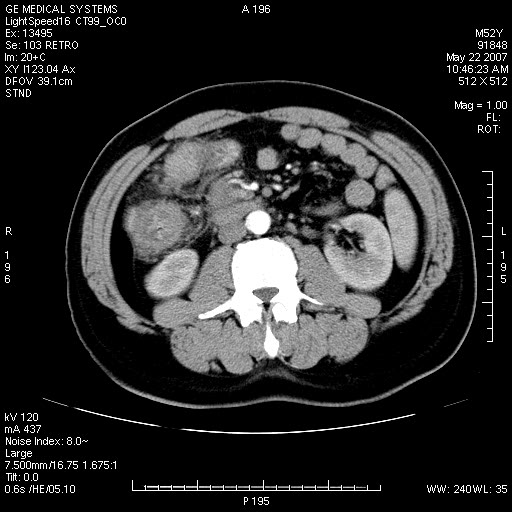

以下是引用余辉在2007-5-22 20:12:00的发言:[br]升结肠管壁明显增厚,增强有静脉期持续增强,结合患者病史,考虑结肠癌可能性大,临近脂肪影密度增高,混浊,恐有肠系膜浸润转移,建议镜检

以下是引用dyqct在2007-5-22 20:43:00的发言:[br]支持结肠肝曲占位性病变(浸润型结肠癌可能性大)。胆总管下端扩张,原因待查。

以下是引用gaoxiao在2007-5-22 20:49:00的发言:[br]考虑升结肠癌向周围侵犯,胰头钩突受侵。